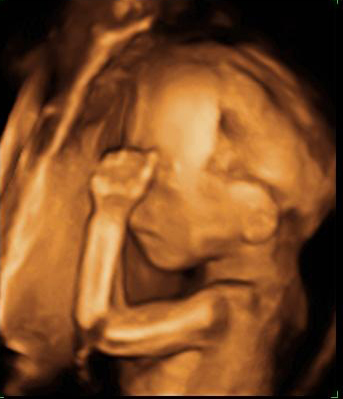

Ecografía semana 20: Cara de perfil y mano del bebé

En la semana 20 de embarazo el bebé aún se mueve libremente dentro del útero materno. Como este feto con la cara de perfil, que se apoya en la pared uterina ayudándose del puño y la nariz. Podemos ver perfectamente la mano cerrada y los dedos, así como los rasgos del perfil y el cráneo.

Cara fetal de perfil y mano frente a la pared del útero

En esta imagen podemos ver cómo el bebé aún tiene sitio para moverse a sus anchas en el útero durante la semana 20 de gestación.

Ecografía Embarazo 4D Semana 20 - MALFORMACIONES FETALES